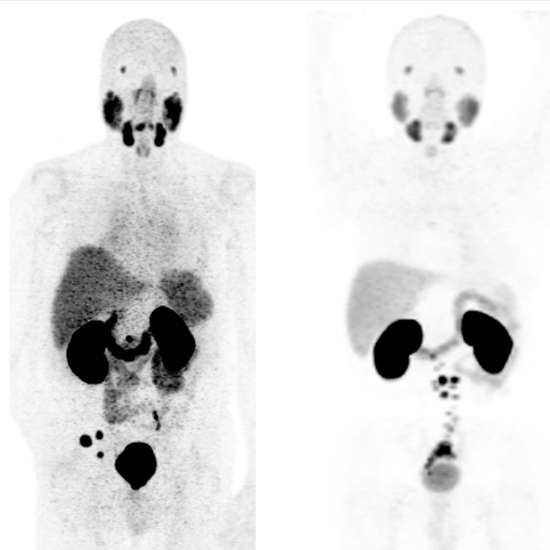

PET PSMA Scan ( prostate-specific membrane antigen scan) is the latest imaging technique for prostate cancer that locate cancer lesions. PSMA PET uses an FDA Approved PET-sensitive drug (68Ga-PSMA-11). This drug attaches to prostate cancer cells and aids in their localization. The most prevalent malignancy among men is prostate cancer. The detection and management of prostate cancer will be greatly enhanced by the novel prostate-specific membrane antigen (PSMA) PET imaging.

The patient will be injected with 68Ga-PSMA-11 radioactive tracer medication. This medication binds to PSMA proteins. Prostate cancer tumors overexpress this protein. The PET scan locates the tumors for more precise treatment because it picks up the concentrated PSMA tracer.

A synthetic radioactive amino acid is injected into patients using a current standard procedure termed fluciclovine PET. It is more accurate prostate cancer detection for improved treatment planning and focused care. It is more efficient in locating and removing cancers that have spread outside of the prostate to other parts of the body and the pelvis. It can detect significantly more prostate lesions than fluciclovine PET in men who had undergone a radical prostatectomy but experienced a recurrence of cancer. It is a more effective and precise technique for localizing metastatic prostate cancer.